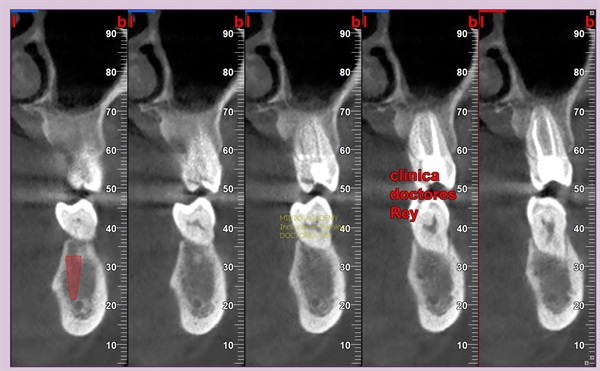

2-Implantes monobloque, en maxilar inferior. MIDI® TECHNIQUE® -US.

4x11,5. colocados con técnica ultarasónica MIDI®, hueso de calidad baja.